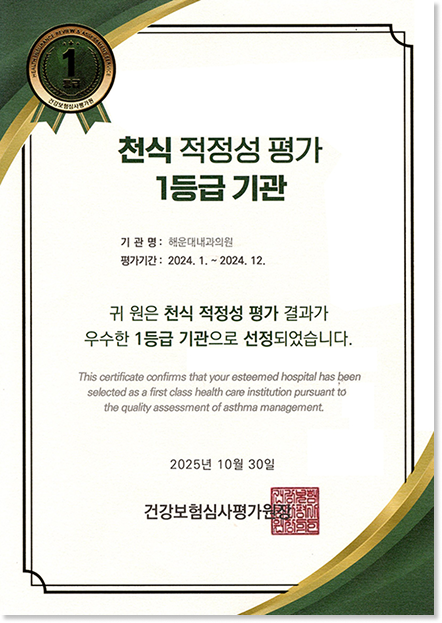

해운대내과 호흡기알레르기클리닉

대한내과학회 인증

최우수 내과전문의 2인 직접 진료